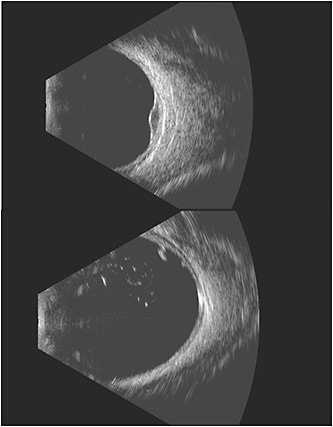

“The ability to choose between the 12 MHz and 18 MHz probe allows for better tailoring of imaging depending on the suspected diagnosis,” Dr. Fuller says (Figure 1). For example, sometimes with choroidal melanoma it is difficult to tell whether there is extraocular extension of the tumor. “The additional resolution can aid in surgical planning for plaque brachytherapy and allow for more appropriate and informed patient counseling.”